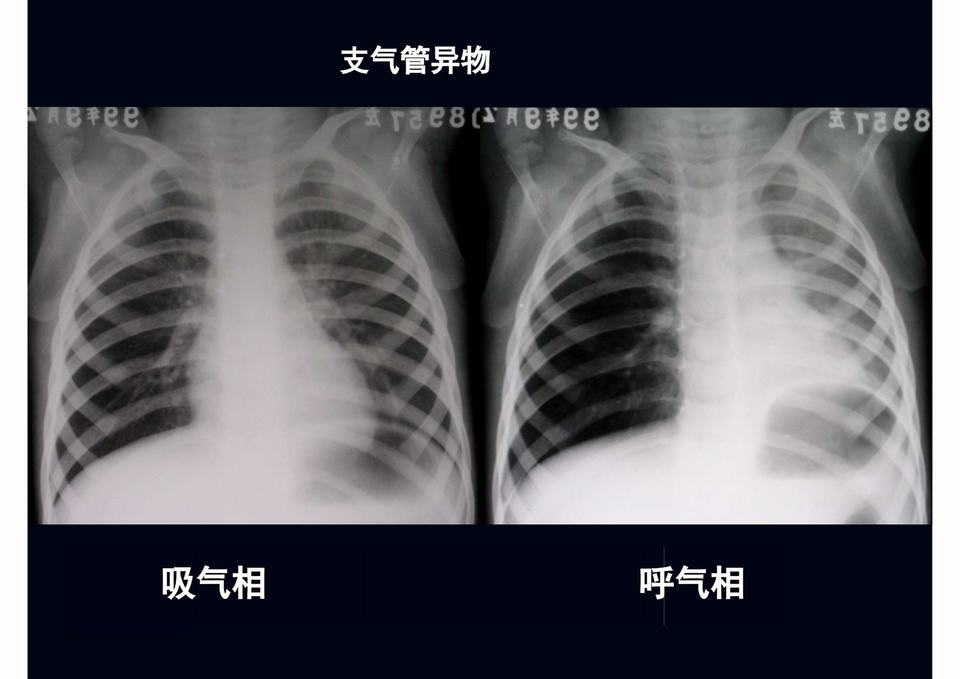

图02